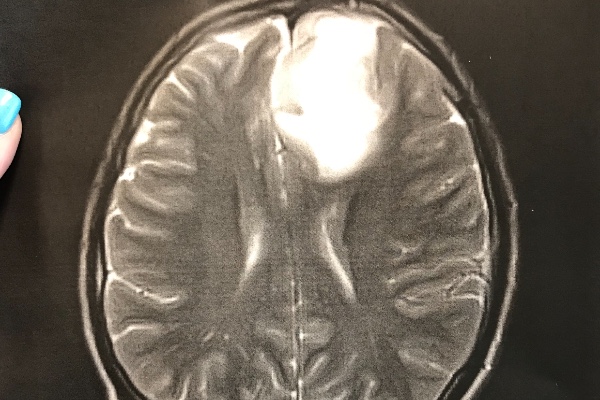

I am starting this for my brother Josh. When Josh was 9 years old he was diagnosed with Type 1 diabetes. He has been in and out of the hospital his whole life. He struggles daily with neuropathy and dealing with his blood sugar. But my brother has always been hard working even when he is in a great deal of pain and would give anyone the shirt off of his back. But last week, things changed. On September 29th, Josh had two seizures back to back while he was at work. He was taken by ambulance to Freeman Hospital in Joplin. There we found out what was causing the seizures. It is a brain tumor. That was the scariest phone call I’ve ever received. Josh will have surgery on October the 10th to have the tumor removed. At this point, they do not think it is cancer. THANK YOU JESUS! But it will be sent off so we will know for sure know what it is and what is causing it after it has been removed. Right now Josh is unable to work and will be unable to work after the surgery for quite some time. I’m starting this campaign to help with his medical expenses, back and forth trips to the Drs and his bills he is unable to pay while he is not working. Most of all, we just want prayers. Prayers that the tumor is 100% not cancer! Prayers that he makes it through the surgery without any complications, and prayers that his recovery is smooth, so he can go back to being a 23 year old young man living his life. But if you can donate, even a $1, I know he would appreciate it. Thank you all for all of the love you have shown us already. Please keep the prayers coming, we appreciate it more than you know. We love Josh so incredibly much and just want to see him well and living his life. Thank you.